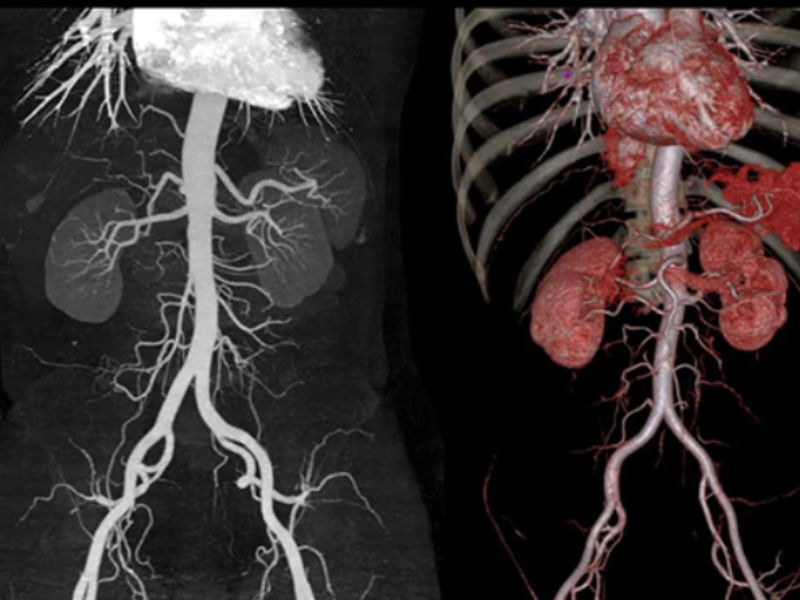

Fine Vascular Structure

80-slice CT withZ-Detector

The ultra-low noise design of the Z-Detector helps produce high image quality with low radiation dose.